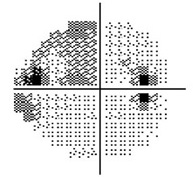

Normal Visual Field

Moderate Visual Field Loss

Severe Visual Field Loss